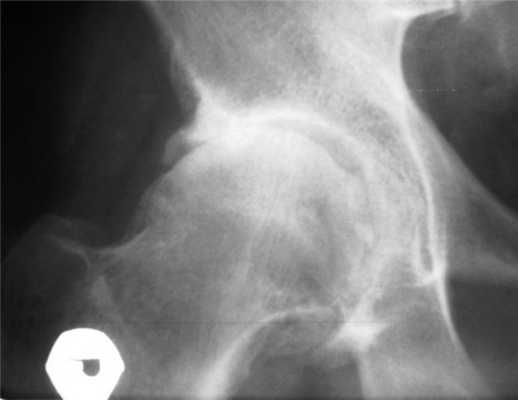

Пациент М., 56 лет, обратился к неврологу с жалобами на боли (до 8 баллов по визуальной аналоговой шкале боли — ВАШ) в правой паховой области, ягодице, передненаружной поверхности ноги до лодыжки, резко усиливающиеся при опоре на ногу. Считает себя больным в течение 2 лет, когда появилась боль в ягодице и наружной поверхности ноги, иногда — в паховой области. Рентгенологическое исследование поясничного отдела позвоночника выявило признаки остеохондроза. Неоднократно по поводу диагностированной неврологом люмбоишиалгии получал НПВП короткими курсами, витамины группы В, физиотерапию с временным положительным эффектом. В течение последних месяцев боль усилилась до интенсивной, преимущественно локализовавшись в паховой области. При осмотре неврологической патологии выявлено не было; другие хронические заболевания отсутствуют. Пальпация проекции щели правого тазобедренного сустава вызывает интенсивную боль. Ортопедический осмотр: резкое ограничение движений в правом тазобедренном суставе; положительные тесты на патологию сустава — Патрика, Дрэхмана, «захвата» Томаса, «наковальни»; движения в пояснице безболезненные. Рентгенологические признаки коксартроза 3—4-й стадии (см. рисунок). Рентгенограмма тазобедренного сустава пациента М. Последующая консультация ортопеда показала необходимость эндопротезирования сустава.